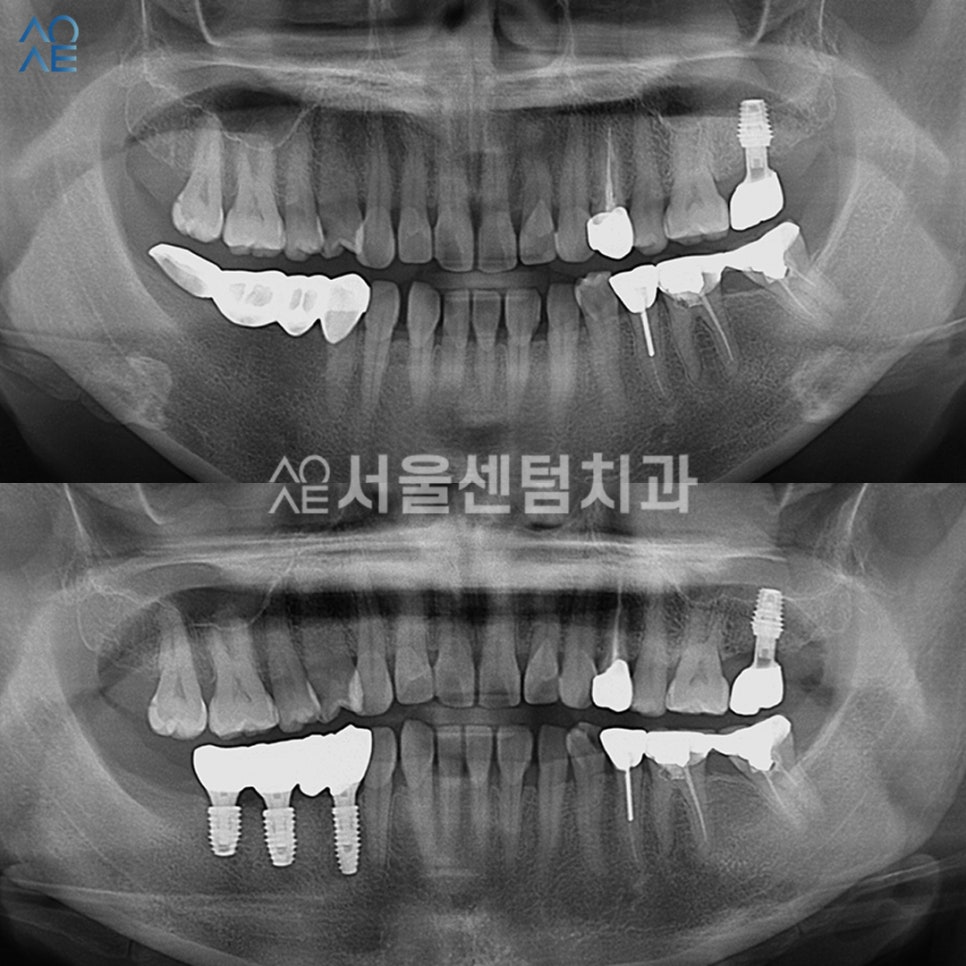

보철물까지 장착 완료한 모습입니다.

총 3개를 식립하긴 하였지만

브릿지 형태로 수복하여서

치아의 기능과 심미성을

올바르게 회복할 수 있게 해드렸습니다.

안정적인 방향으로 잘 식립되었고

뼈이식도 성공적으로 잘 되었습니다.

보철물 부착 후에도 체크를 진행하였습니다.

다행히 세팅 후 불편함은 없고

지금은 자연치아처럼 편하게 사용중이십니다.